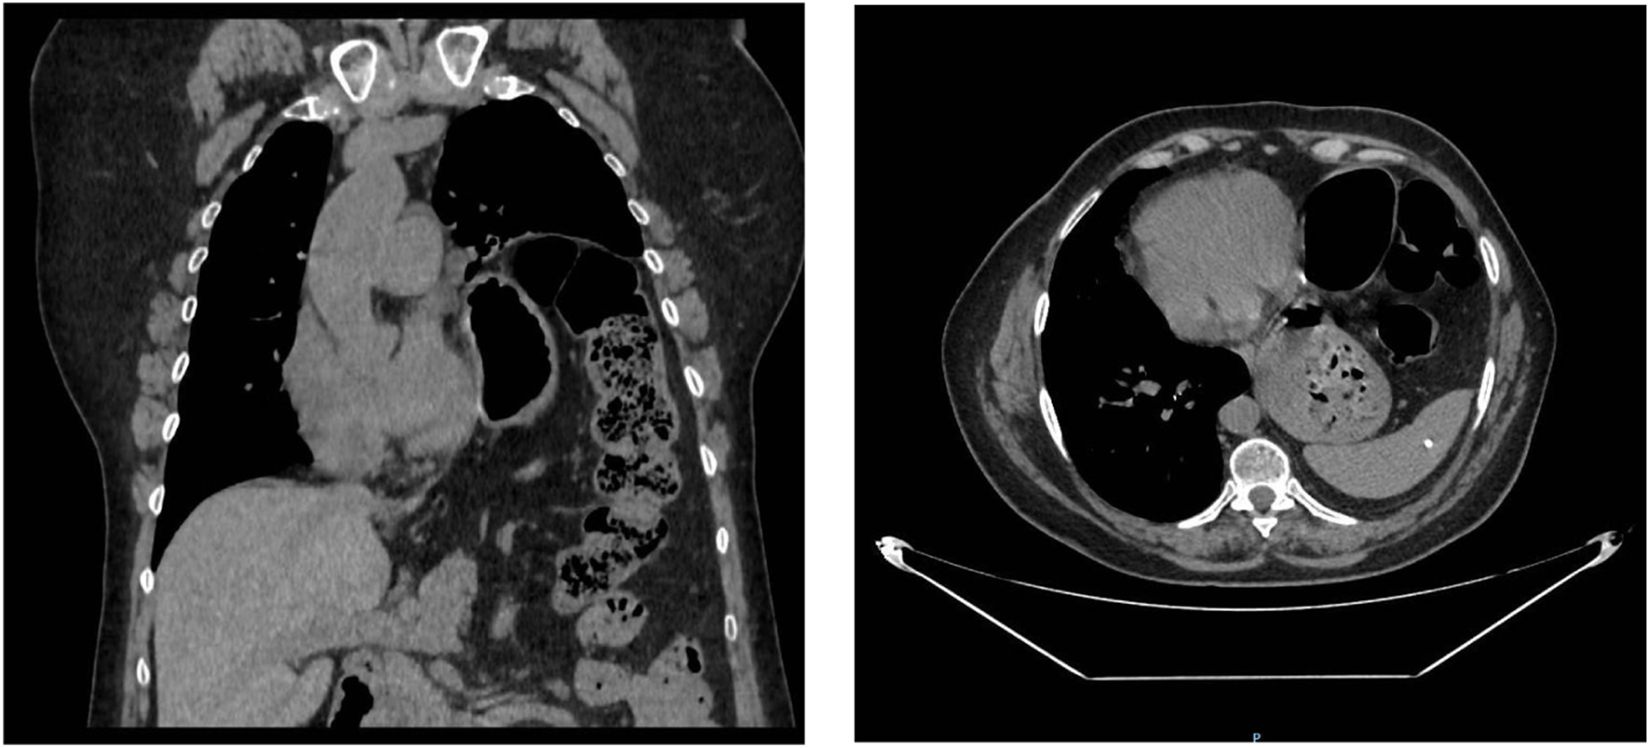

A chest CT (Figure 3) scan revealed a severe elevation of the left hemidiaphragm and herniation of abdominal contents into the thorax, including stomach, spleen, and colon splenic flexure, with a percentage of herniated viscera of 23% according to Sabagg’s formula [13], which occupied more than half of the left hemithorax. It is associated with compressive atelectasis and a moderate contralateral mediastinal shift. No image of a diaphragmatic defect was observed. Preoperative preparation focused on prehabilitation with chest physiotherapy. Given the size of the defect, adjuvant therapy was performed with botulinum toxin injection following the Smoot technique [14], without complications.

FIGURE 3

Computed tomography (coronal and transverse section) marked elevation of the left hemidiaphragm and herniation of abdominal contents into the thoracic cavity, including the stomach, spleen, and splenic flexure of the colon with a moderate contralateral mediastinal shift.